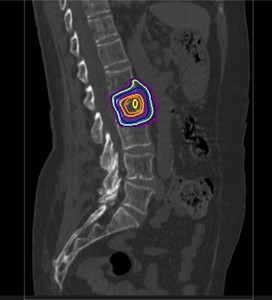

当科では治療用のCT(富士フィルム SCENARIA64列)、3次元治療計画装置(Ray Search社 Ray Plan)、ライナック(ELEKTA社 Precise Treatment System)が設置されています。CTシミュレーターを用いた3次元治療計画を行い、多方向から病巣へ線量を集中させて最大限の効果をねらうと同時に、周囲臓器への被曝を減らして副作用を最小限に止めるよう努めています。

骨転移に集中した3次元治療計画の線量分布図